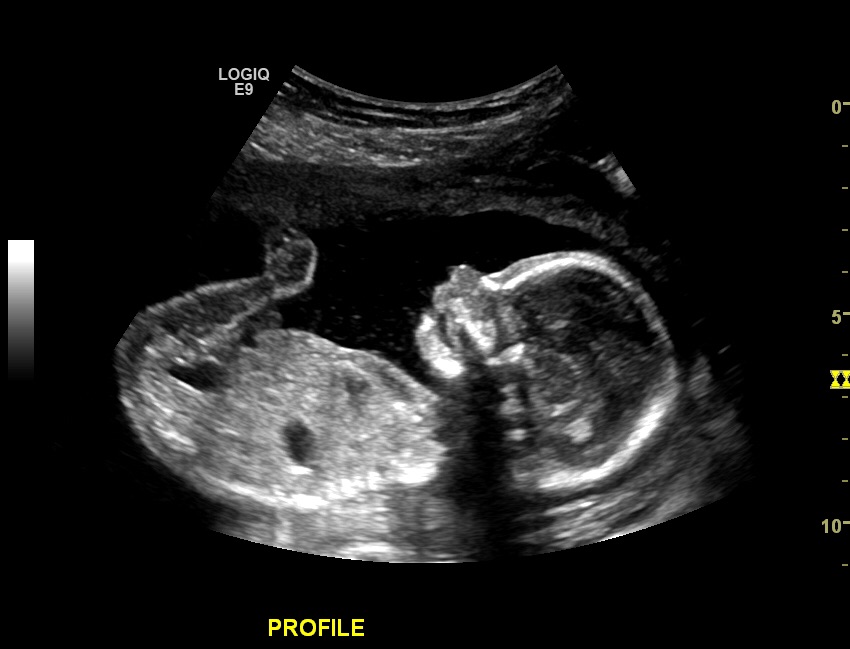

Had my anatomy this morning and was extremely relieved to see him look so handsome and healthy thank God. I was also very nervous last night especially since I didn't start feeling him kick until a couple days ago. It turns out my placenta implanted on top therefore baby has to kick through it for me to feel it. I am now going relax and enjoying the last half of my pregnancy. I couldn't be happier.

So relieved and happy we have a healthy, normal, and active BOY. Suprised cause everyone has said it was a girl. We could have cared less either way. So nice to see him moving around and that he has 10 fingers and toes. Was super nervous prior. Phew!!!!